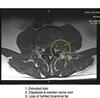

You have what is known in ordinary language as a slipped disc. The soft gel in the disc has slipped out of its ring and is now in the small foramen where the nerve leaves the spine.